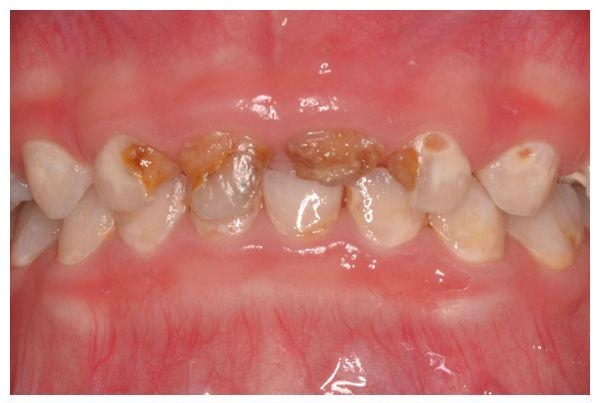

儿童龋齿治疗

四手操作下治疗儿童牙病